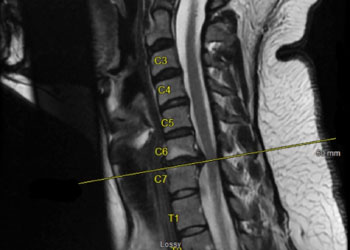

Below are the pre-operative MRI cervical spine images showing a left-sided C6/C7 herniated disc with pressure on the existing left C7 nerve root.